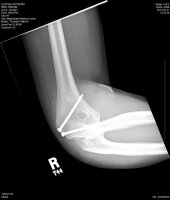

In all seriousness Ray I hope you heal up quickly. I dont know how old these images are, but man that had to really hurt like a SOB!

about 2 weeks :devil: it wasnt too bad, i manned up and didnt cry. but thank you very much!